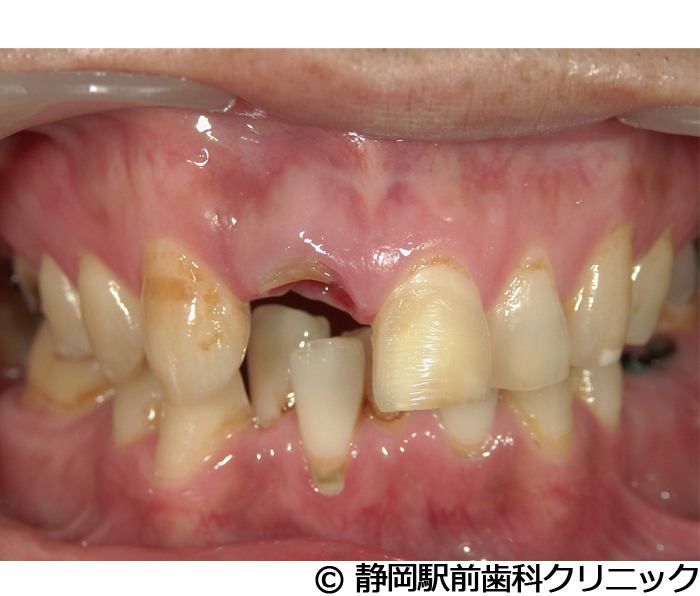

【症例2】上顎前歯単独インプラント埋入

- 治療前

- 治療後

- 治療名

- 上顎前歯単独インプラント埋入

- 費用

- 385,000円(税込)

- 期間

- 7ヵ月

治療内容

-

患者様の症状

上の前歯の入れ歯を使っていたが、違和感があるし、毎日手入れが大変なのでインプラント治療希望。

治療方法

術前にCTや歯型などの資料を取り、前歯のため審美性も考慮し、綿密に治療計画を立てました。その後、インプラントを埋入し、人工歯を被せて審美と咬合の回復を行いました。

治療結果

自分の歯のような見た目で、違和感もなく噛むことができてご満足いただくことができました。

※治療結果は個人差があります。

治療を行う上での注意点(リスク・副作用)

術後は、出血、腫れ、痛みなどが出る可能性があります。